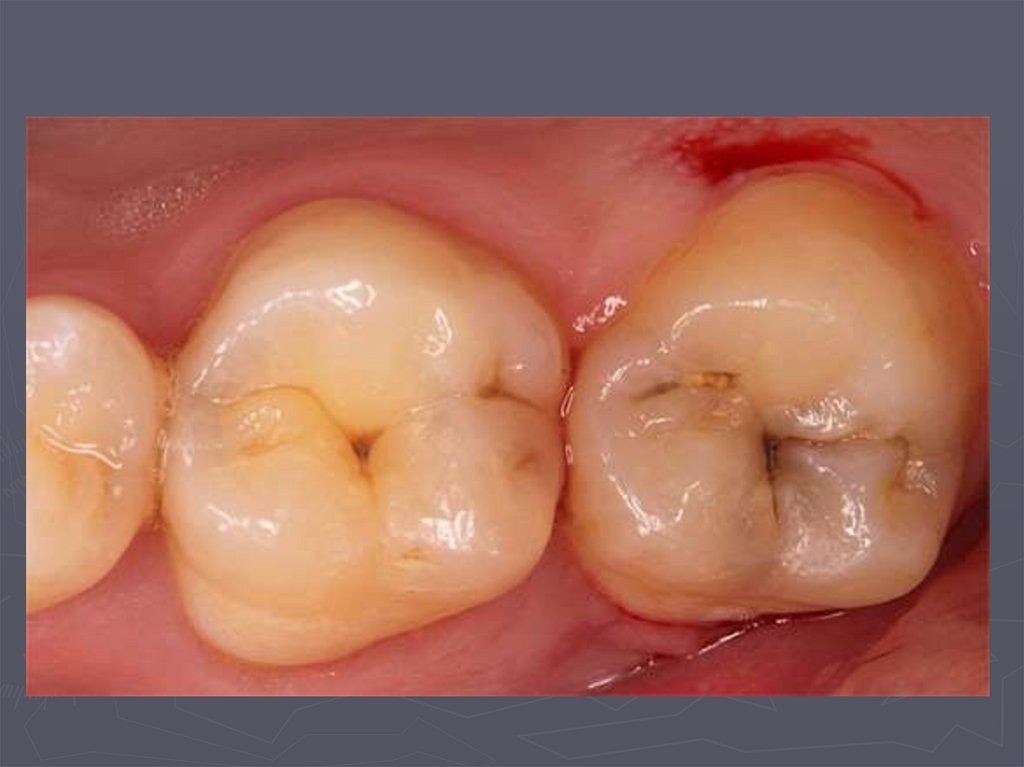

37. КЛИНИЧЕСКАЯ КАРТИНА СРЕДНЕГО КАРИЕСА при компенсированной форме:

► отмечается быстропроходящая боль от

химических, термических, иногда от

механических, раздражителей;

► края кариозной полости закругленные, ровные;

► эмаль плотная;

► дентин плотный, пигментированный;

► при зондировании болезненность определяется

по эмалево-дентинному соединению.

38. КЛИНИЧЕСКАЯ КАРТИНА СРЕДНЕГО КАРИЕСА при декомпенсированной форме:

► при локализации кариозной полости в фиссурах

определяется небольшое входное отверстие;

► при раскрытии обнаруживается кариозная

полость с податливым дентином;

► края кариозной полости нависают;

► эмаль тонкая, хрупкая;

► дентин светлый, влажный, размягченный, легко

удаляется экскаватором;

► зондирование болезненно по

эмалево-дентинному соединению.